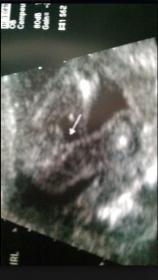

What makes me wonder is that it looks like something is pushed over to the left. the left leg at the bottom looks thicker than the other. I know its small on here, I wish I could make it bigger.

It's probably cord, if anything...

I do see the area you are talking about when I zoom in. Not sure what it is. Doesn't really look like a scrotum. But stranger things have happened!